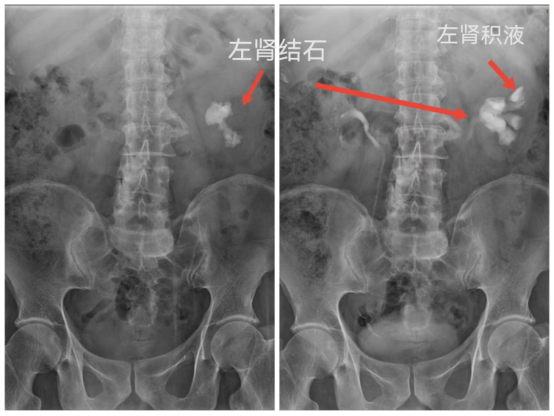

常规拍腹部仰卧位平片(KUB),准备好腹部压迫带,静脉注射造影剂,同时腹部加压,注射完后分别于7、15、30分钟摄片及解除压迫后摄片。

IMG_259IMG_260IMG_261IMG_262

静脉肾盂造影用于检查泌尿道器质性病变,可观察到尿路梗阻部位及原因。显示尿路结石造成的造影充盈缺损,对泌尿系病变有重要的诊断意义,静脉肾盂造影是放射科的常规检查项目,为进一步治疗提供可靠的指导意见及治疗方案。(供稿:放射科)